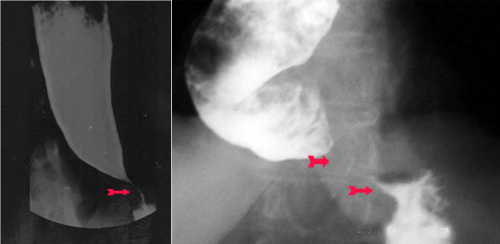

- צילום הוושט לאחר בליעת בריום, או CT בטן עם חומר ניגוד המראה האופייני הוא של משפך ומדיאסטינום רחב. התמונה הרנטגנית האופיינית של משפך נוצרת עקב חסימה באזור הקרדיה, הגורמת להתרחבות הוושט מעליה ואילו האזור החסום הוא צר ונראה לעתים כספירלה.

הגישה הניתוחית המקובלת ביותר היא כריתת שריר בוושט ובקרדיה (אזופאגו-קרדיומיוטומיה - Esophago-cardiomyotomy) - הניתוח על-שם Heller. ניתוח זה מתבצע דרך תורקוטומיה (פתיחת בית חזה) שמאלית, חשיפת הוושט והקרדיה וחיתוך שרירי דופן הוושט בחתך אחד לכל עוביים, החל מהקרדיה, 2-1 ס"מ על הקיבה, ועד מעל להיצרות (8-6 ס"מ) (איור 10.1 א-ב). בגמר הניתוח הרירית נראית שלמה ובולטת דרך החתך בוושט. כדי למנוע היווצרות של בקע סרעפתי יש להימנע מפגיעה במבנים בתוך ההיאטוס בזמן החיתוך. אין כל צורך לבצע ואגוטומיה (כריתת עצבי התועה) ופילורופלסטיקה במקרים אלה. להפך, יש לשמר את עצבי התועה. יש הממליצים לבצע פונדופליקציה לאחר מיוטומיה כדי למנוע רפלקס של חומצה לוושט ואזופאגיטיס (איור 10.1 ג).